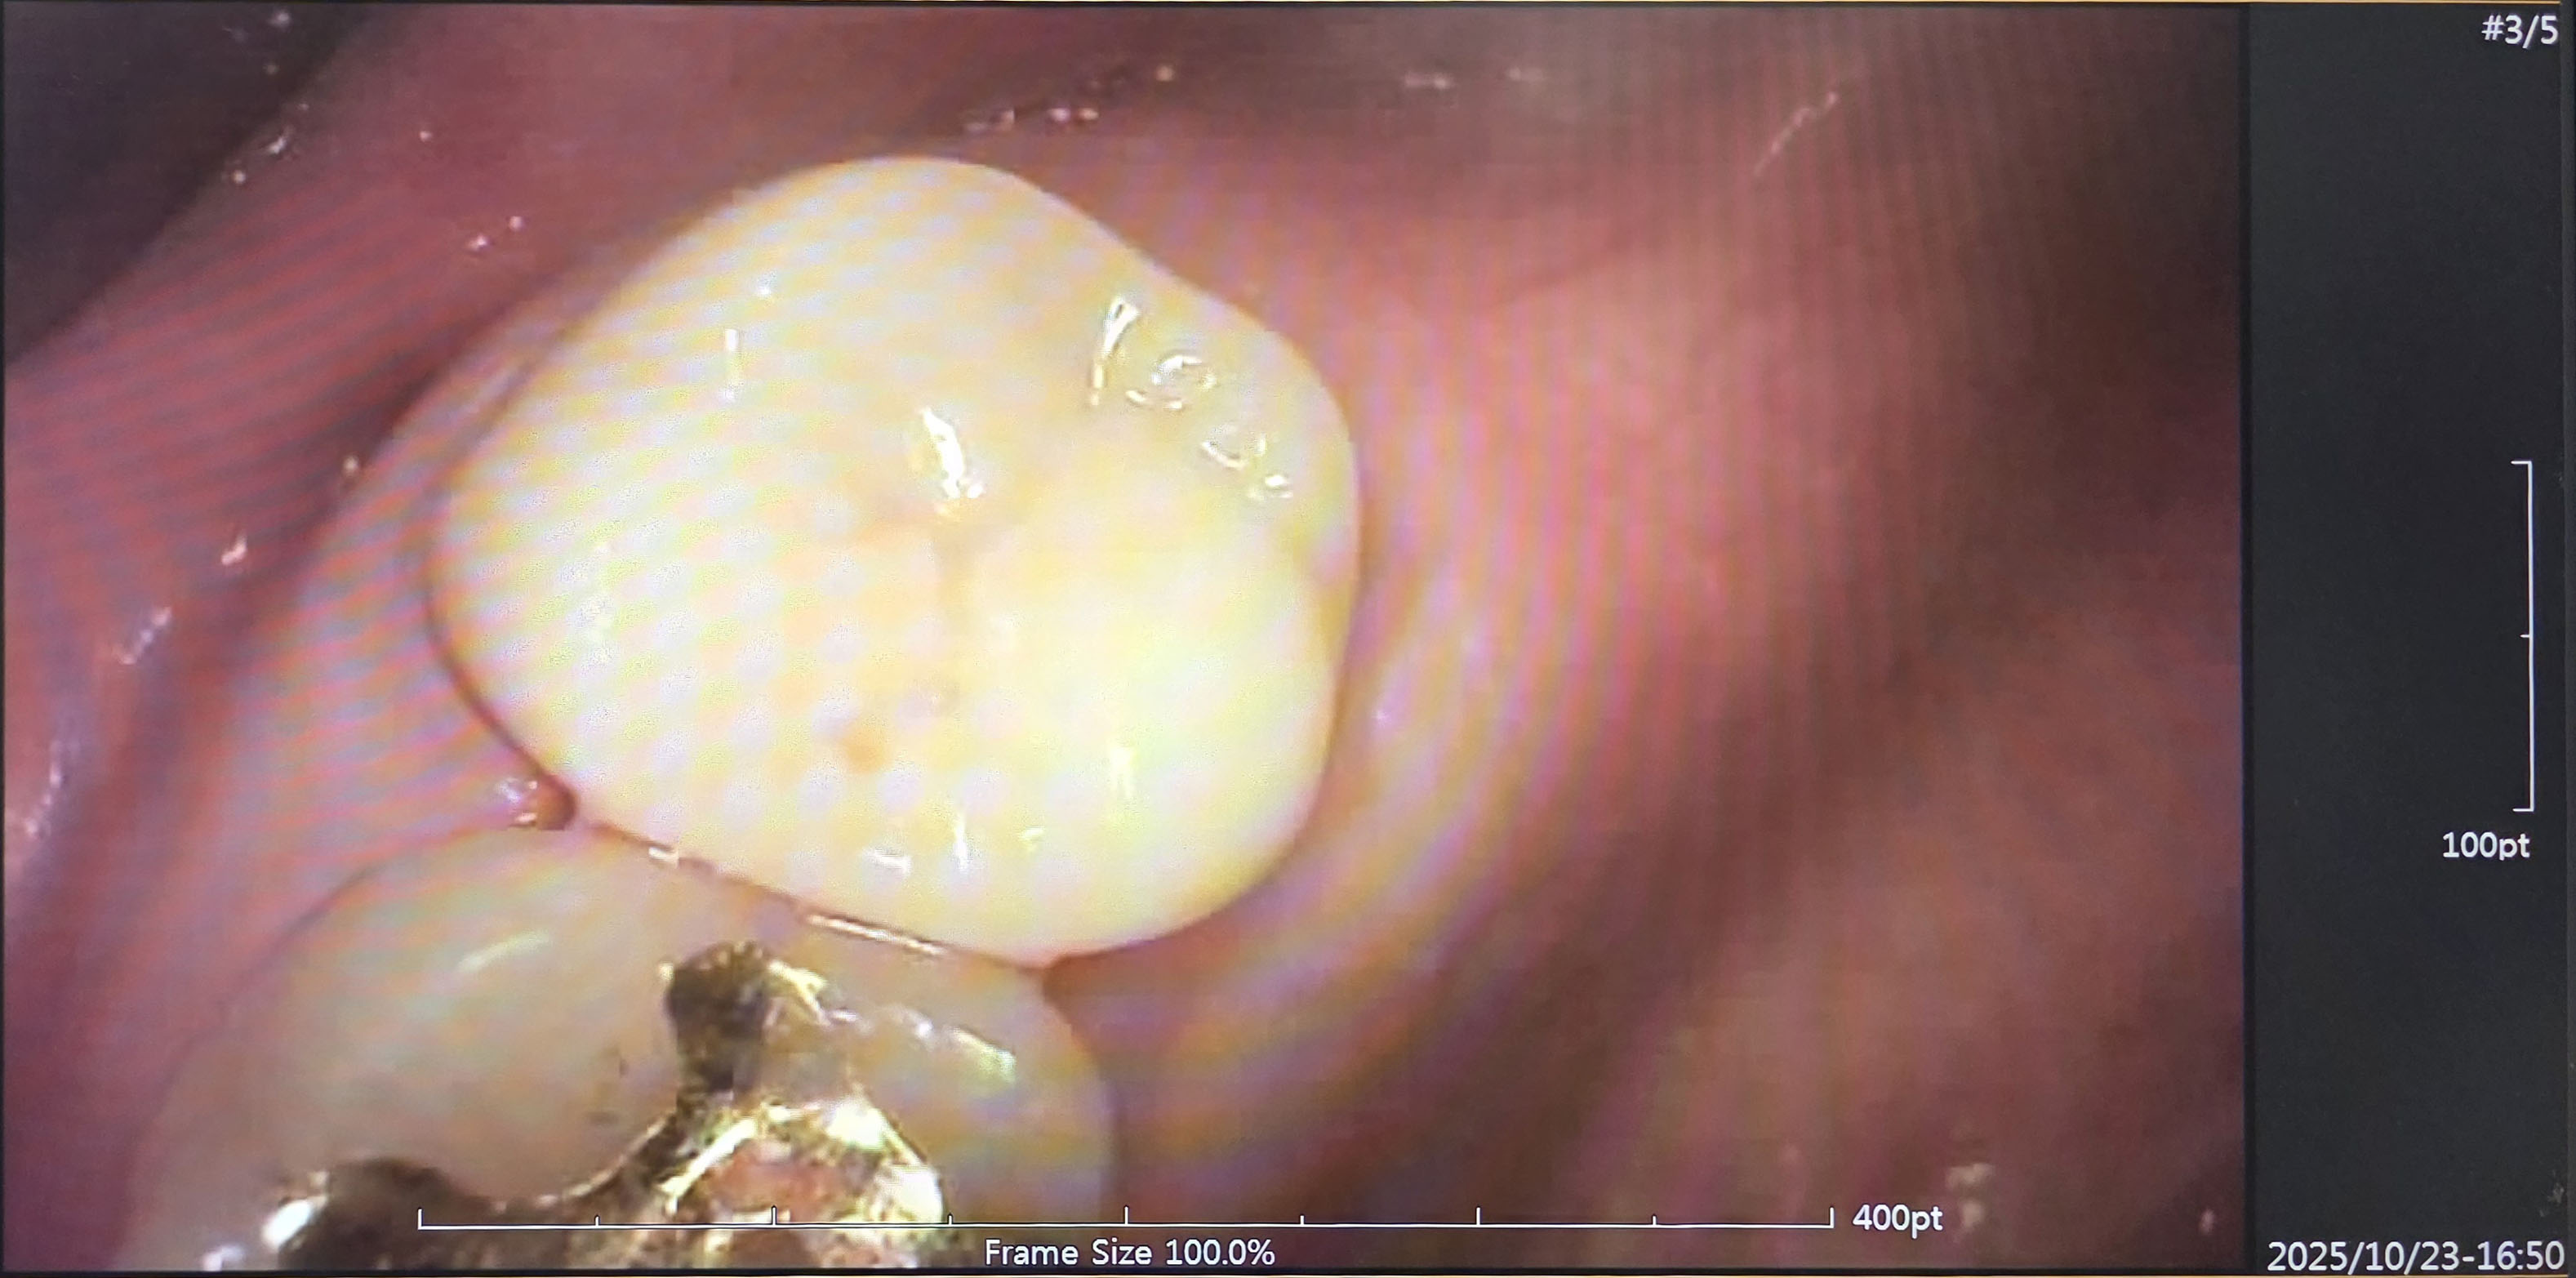

마지막 신경치료까지 마친 치아 상태입니다. 저는 봐도 모르겠습니다.

뿌리까지 신경치료를 모두 잘 치료했다고 들었어요!